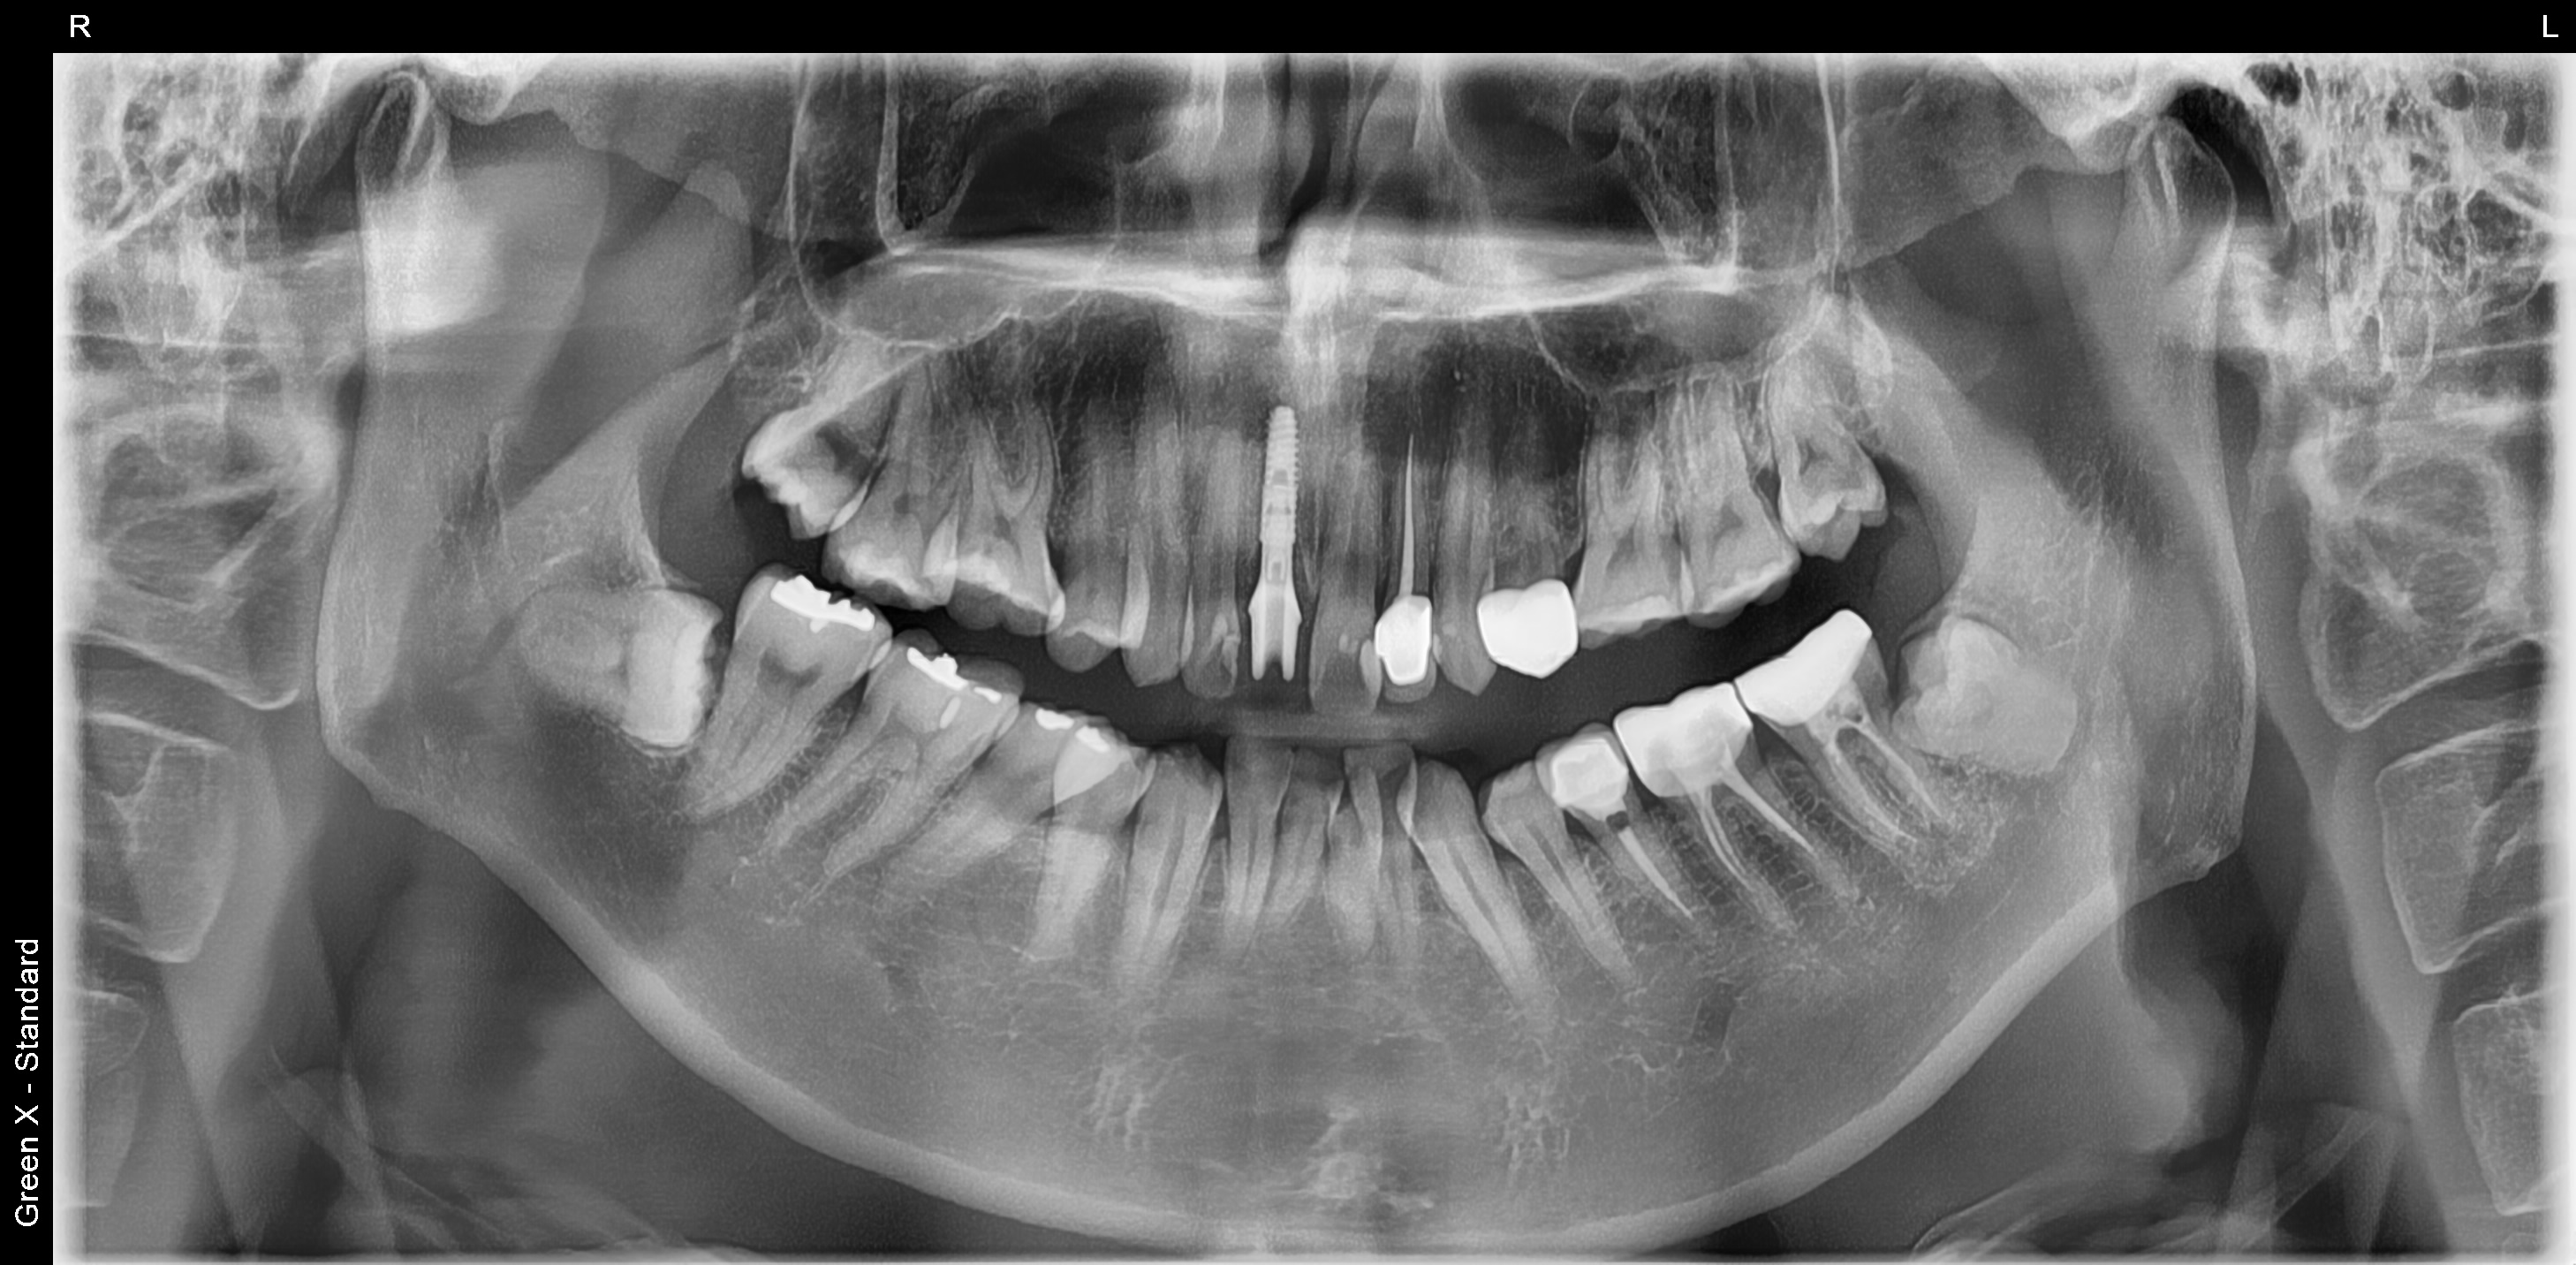

30대 남성분이 넘어져서 앞니가 흔들린다고 고촌치과에 내원하셨습니다.

CT 검사 결과 치아 머리 부분이 부러졌습니다.

살릴 수는 없는 상황이라 발치 즉시 임플란트와 즉시 임시치아를 계획하였습니다.

임플란트 식립후 임시치아를 바로 제작한 후 사진입니다.

아래는 3개월 후 최종 보철 후 사진입니다.